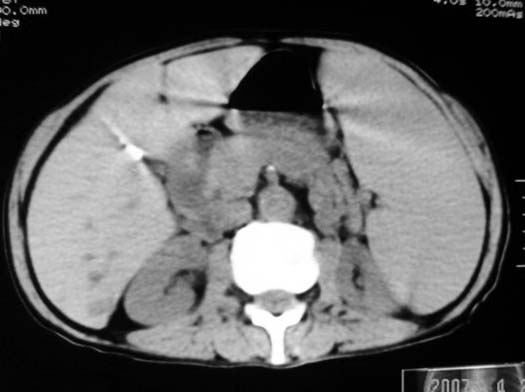

以下是引用dyqct在2007-4-20 16:38:00的发言:[br]考虑:1、巨脾;[br] 2、肝内多发低密度,首先考虑转移瘤;[br] 3、胆囊多发结石。